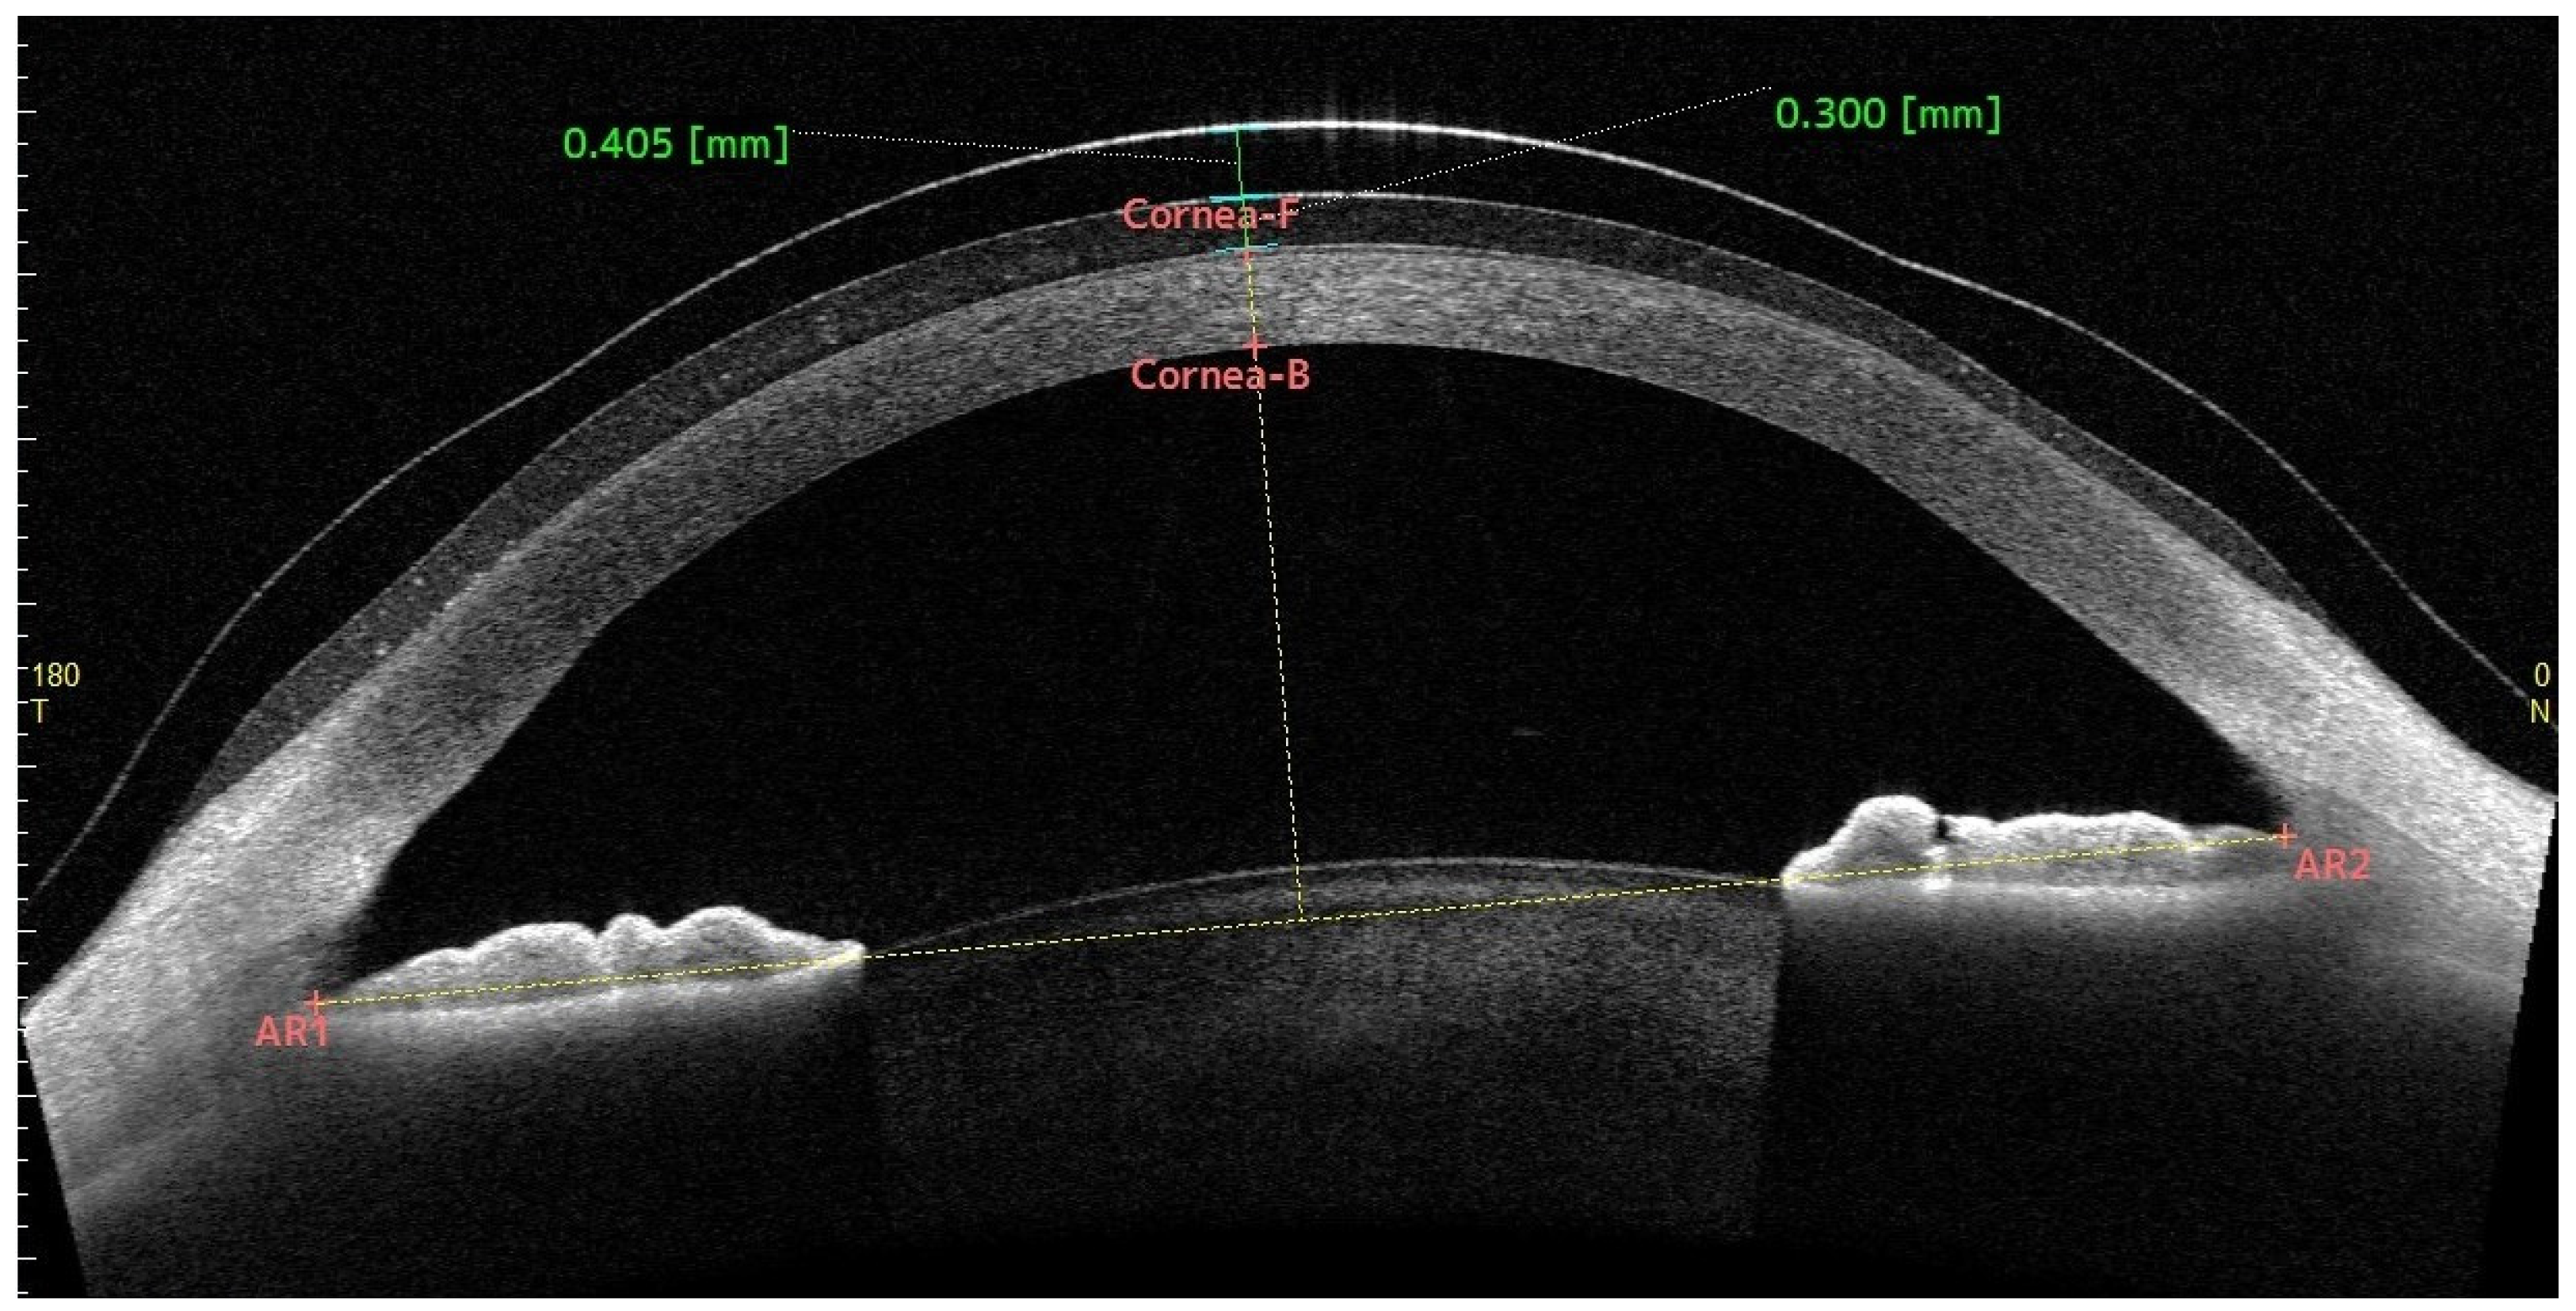

3.2. Central Fluid Reservoir

3.3. Central Corneal Thickness